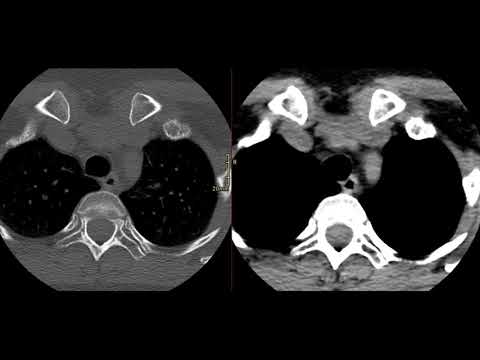

Укладка КТ коленных суставов натив

Видеоурок по позиционированию области исследования для рентгенолаборантов. Остались непонятные моменты? Задавайте свои вопросы под видео, и наши эксперты ответят на них. А может вы уже знаете, какую укладку хотите увидеть следующей? Подписывайтесь на наш канал, нажимайте "колокольчик" рассказывайте о том, что вы хотите изучать и прокачивайте свои навыки. Социальные сети Центра диагностики и телемедицины: Telegram: